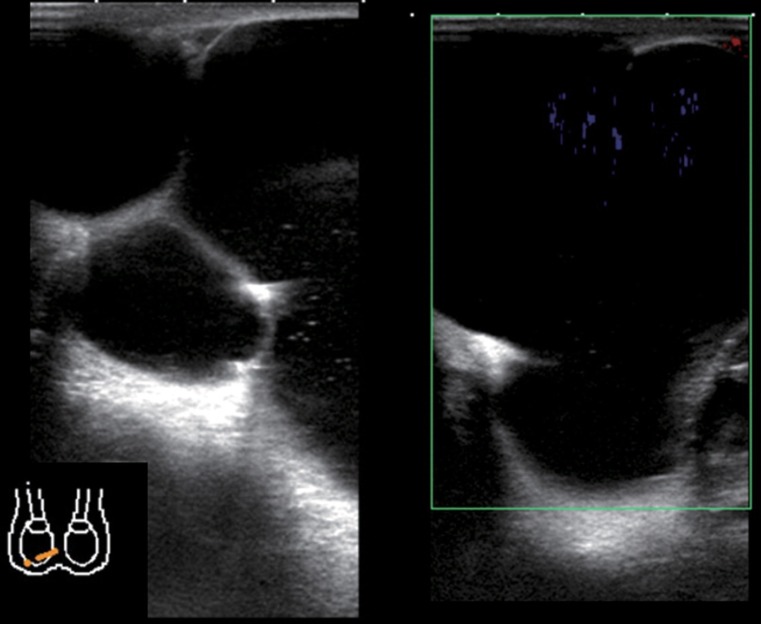

Lymphatic malformation/lymphangioma of the scrotum is rare. It is caused by lymphatic abnormalities and the most common sites are the neck and axilla. The scrotum is one of the most uncommon sites. We report the case of a 12-year-old boy with pathologically confirmed cystic lymphangioma/lymphatic malformation in the scrotum. The diagnosis was suspected from ultrasonography and magnetic resonance imaging. The most common cause of a cystic mass in the scrotum is scrotal hydrocele, but cystic lymphangioma/lymphatic malformation should be considered as a differential diagnosis for multicystic scrotal mass.